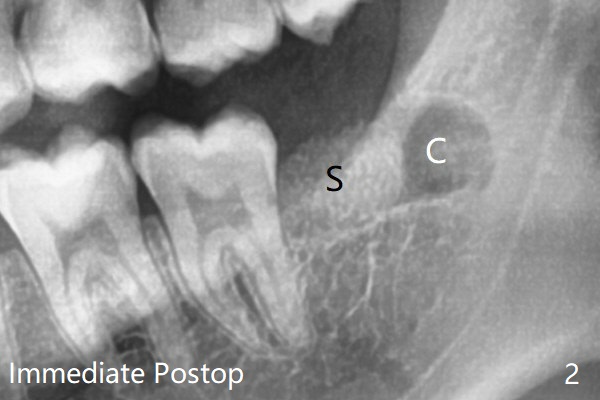

所以拔牙(多次切割)后,半块胶原塞放置于牙槽窝根尖(图二:C),而粘性骨粉牙槽窝牙冠,即第二磨牙远中(S),之上又放置半块胶原塞和两块PRF膜,促使伤口愈合,防止干槽症。